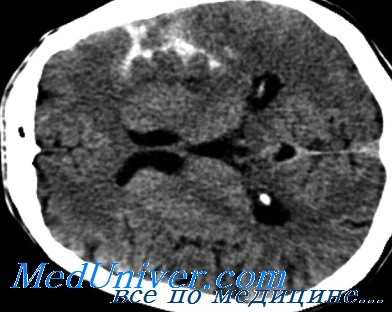

КТ головного мозга. Геморрагический инсульт, обширная интрапаренхиматозная гематома в левой гемисфере

Они позволяют определить объем и локализацию внутримозговой гематомы, степень дислокации мозга и сопутствующего отека, наличие и область распространения кровоизлияния. Желательно проведение повторных КТ-исследований, чтобы проследить эволюцию гематомы и состояние мозговой ткани в динамике.